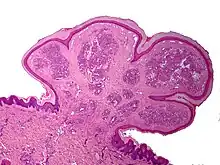

One study has suggested a correlation between pyogenic granulomas and Bartonella seropositivity.[5] However, this association has been questioned by others.[6] The microscopic appearance of a pyogenic granuloma consists of highly vascular granulation tissue. Inflammation is present. The lesion may have a fibrous character if it is older, and the surface may have ulcerations. Pyogenic granulomas rarely occur in the conjunctiva, cornea, or connective tissue of the eye following minor local trauma. Grossly, these mass lesions resemble those occurring at more common sites. The relationship of these lesions to lobular capillary hemangiomas of skin and oropharyngeal mucosa commonly referred to as pyogenic granuloma is uncertain.

Histopathological examination shows multiple capillaries (due to the vascular nature of the tumor), neutrophils (pyogenic), and necrotic tissue.